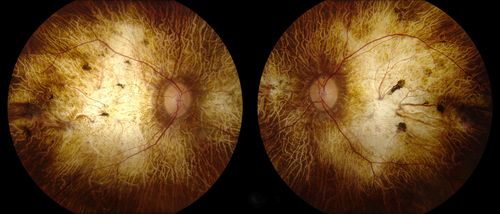

Chorodial Sclerosis

74 year old female diagnosed with Chorodial Sclerosis OU and ARMD OU. Va 20/400 OD 2'200 OS

wet amd, choroid, sclerosis, chorodial

Nicholas Leonard Carolina Eye Associates, P.A. North Carolina

Topcon TRC 50DX